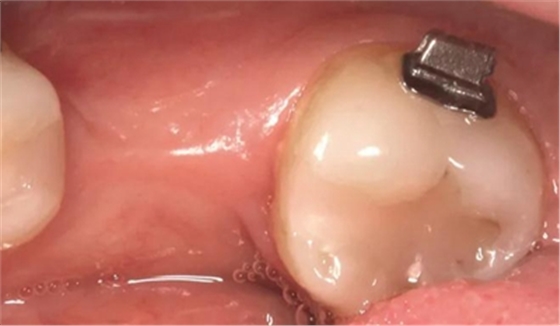

圖2d. 3個(gè)月后,獲得顯著的骨增量,同時(shí)創(chuàng)造出1.6mm的近遠(yuǎn)中修復(fù)空間

術(shù)后即刻,將0.018×0.025英寸的銅鎳鈦(NiTi)弓絲和NiTi 主弓絲套推簧沿著無(wú)牙頜區(qū)域置于雙側(cè),施加半托槽寬度(約1.5mm)的力?;颊咴谧畛醯?個(gè)月中,每2周隨訪(fǎng)一次,之后每月隨訪(fǎng)一次。1個(gè)月后,左側(cè)下頜第一磨牙區(qū)獲得了10mm的近遠(yuǎn)中距離,用被動(dòng)線(xiàn)圈保持。對(duì)側(cè)區(qū)域(右側(cè)第一磨牙)空間通過(guò)主弓絲套推簧和三線(xiàn)圈來(lái)加力(一個(gè)托槽的寬度)。術(shù)后3個(gè)月時(shí),達(dá)到10mm的目標(biāo)(圖2d)。分別在術(shù)前(圖3a)和骨增量5個(gè)月后(圖3b)拍攝右下頜第一磨牙區(qū)域的錐束CT,結(jié)果顯示,成功獲得了5mm的水平骨增量。這樣的增量允許在合適的位置上植入一個(gè)寬直徑的種植體。

圖5g. 3 個(gè)月后完成了位點(diǎn)加速改建,近遠(yuǎn)中向的修復(fù)空間和頰舌向的骨增量均增加

術(shù)后3個(gè)月,右側(cè)第一磨牙的空間約為9mm(3個(gè)月中增加了1.6mm),逐漸接近了對(duì)側(cè)第一磨牙的空間(也約9mm)(圖6a)。術(shù)后7個(gè)月的錐束CT顯示,右側(cè)第一磨牙區(qū)域獲得了2.5mm的水平骨增量(圖6b 和c)。左側(cè)第一磨牙的無(wú)牙區(qū)保持相同的尺寸,在種植體植入前也需要骨增量。